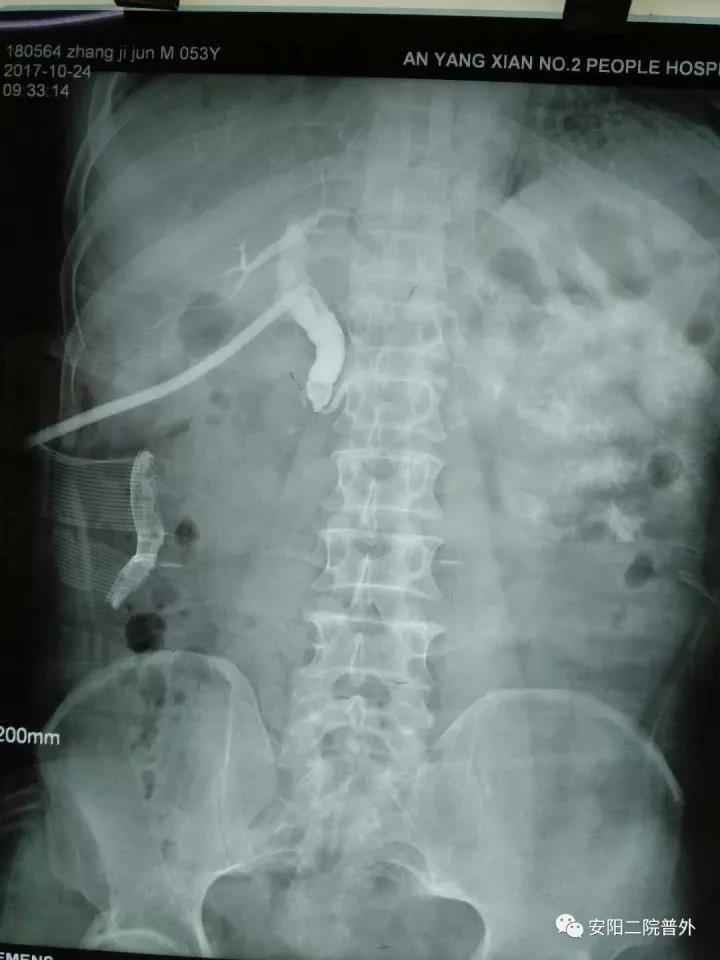

該例患者男性,52歲,外院行“膽囊切除+膽總管探查+T管引流術(shù)”,術(shù)后兩個(gè)月T管造影示:造影劑排入十二指腸受阻,膽總管擴張,膽總管下段見(jiàn)略低密度影,考慮膽總管下段結石?;颊哂诙嗉胰揍t院就診,因結石較大病情復雜未能入院治療。而后患者慕名找到普外科孟鈺主任,孟主任綜合評估后收住院,完善檢查后行膽道鏡檢查:術(shù)中見(jiàn)膽總管下段結石嵌頓,直徑約1.5cm,抓鉗及取石籃取石失敗,遂與泌尿外科張新軍主任聯(lián)合,行膽總管結石鈥激光碎石術(shù),將結石粉碎成小塊結石和粉末狀結石,取出小塊結石,將粉末狀結石沖洗入十二指腸,手術(shù)順利。目前患者康復出院。

內鏡下的膽總管結石

取石前